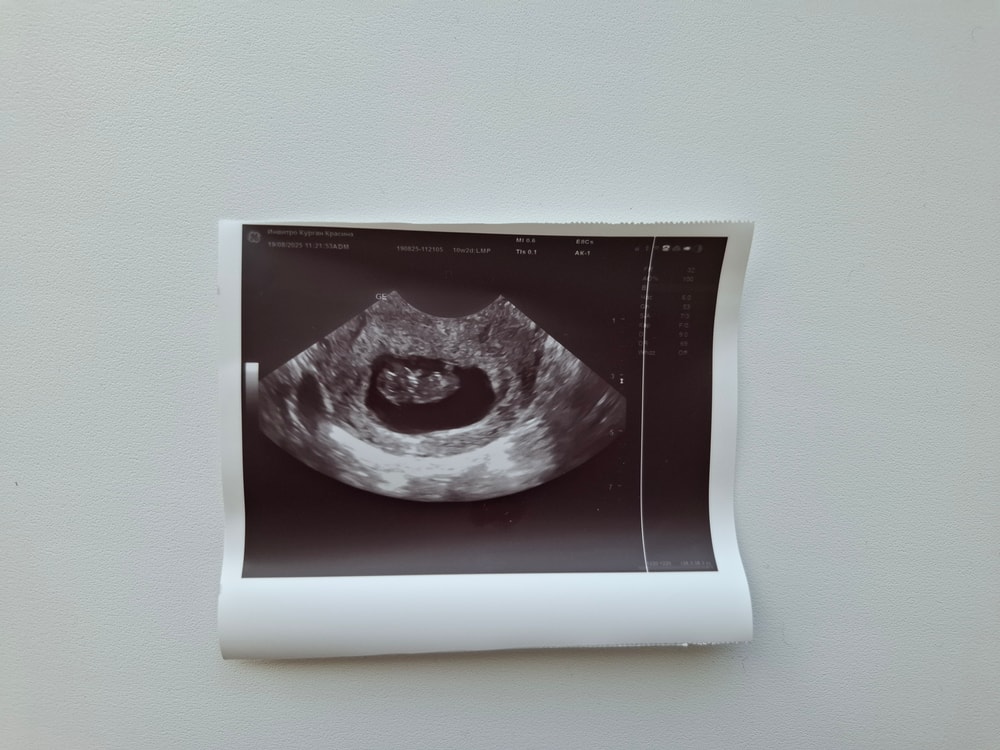

Сегодня сходила на узи, не виделись с малышом уже неделю😀 Бооожеееее, он шевелит ручками,ножками- показали на экране, я чуть не расплакалась 🥰 Вырос уже до 2,9 см, СБ 172 уд/мин ( соответствует 9н5д). Жду результата НИПТ, очень интересно кто же там растет🥰